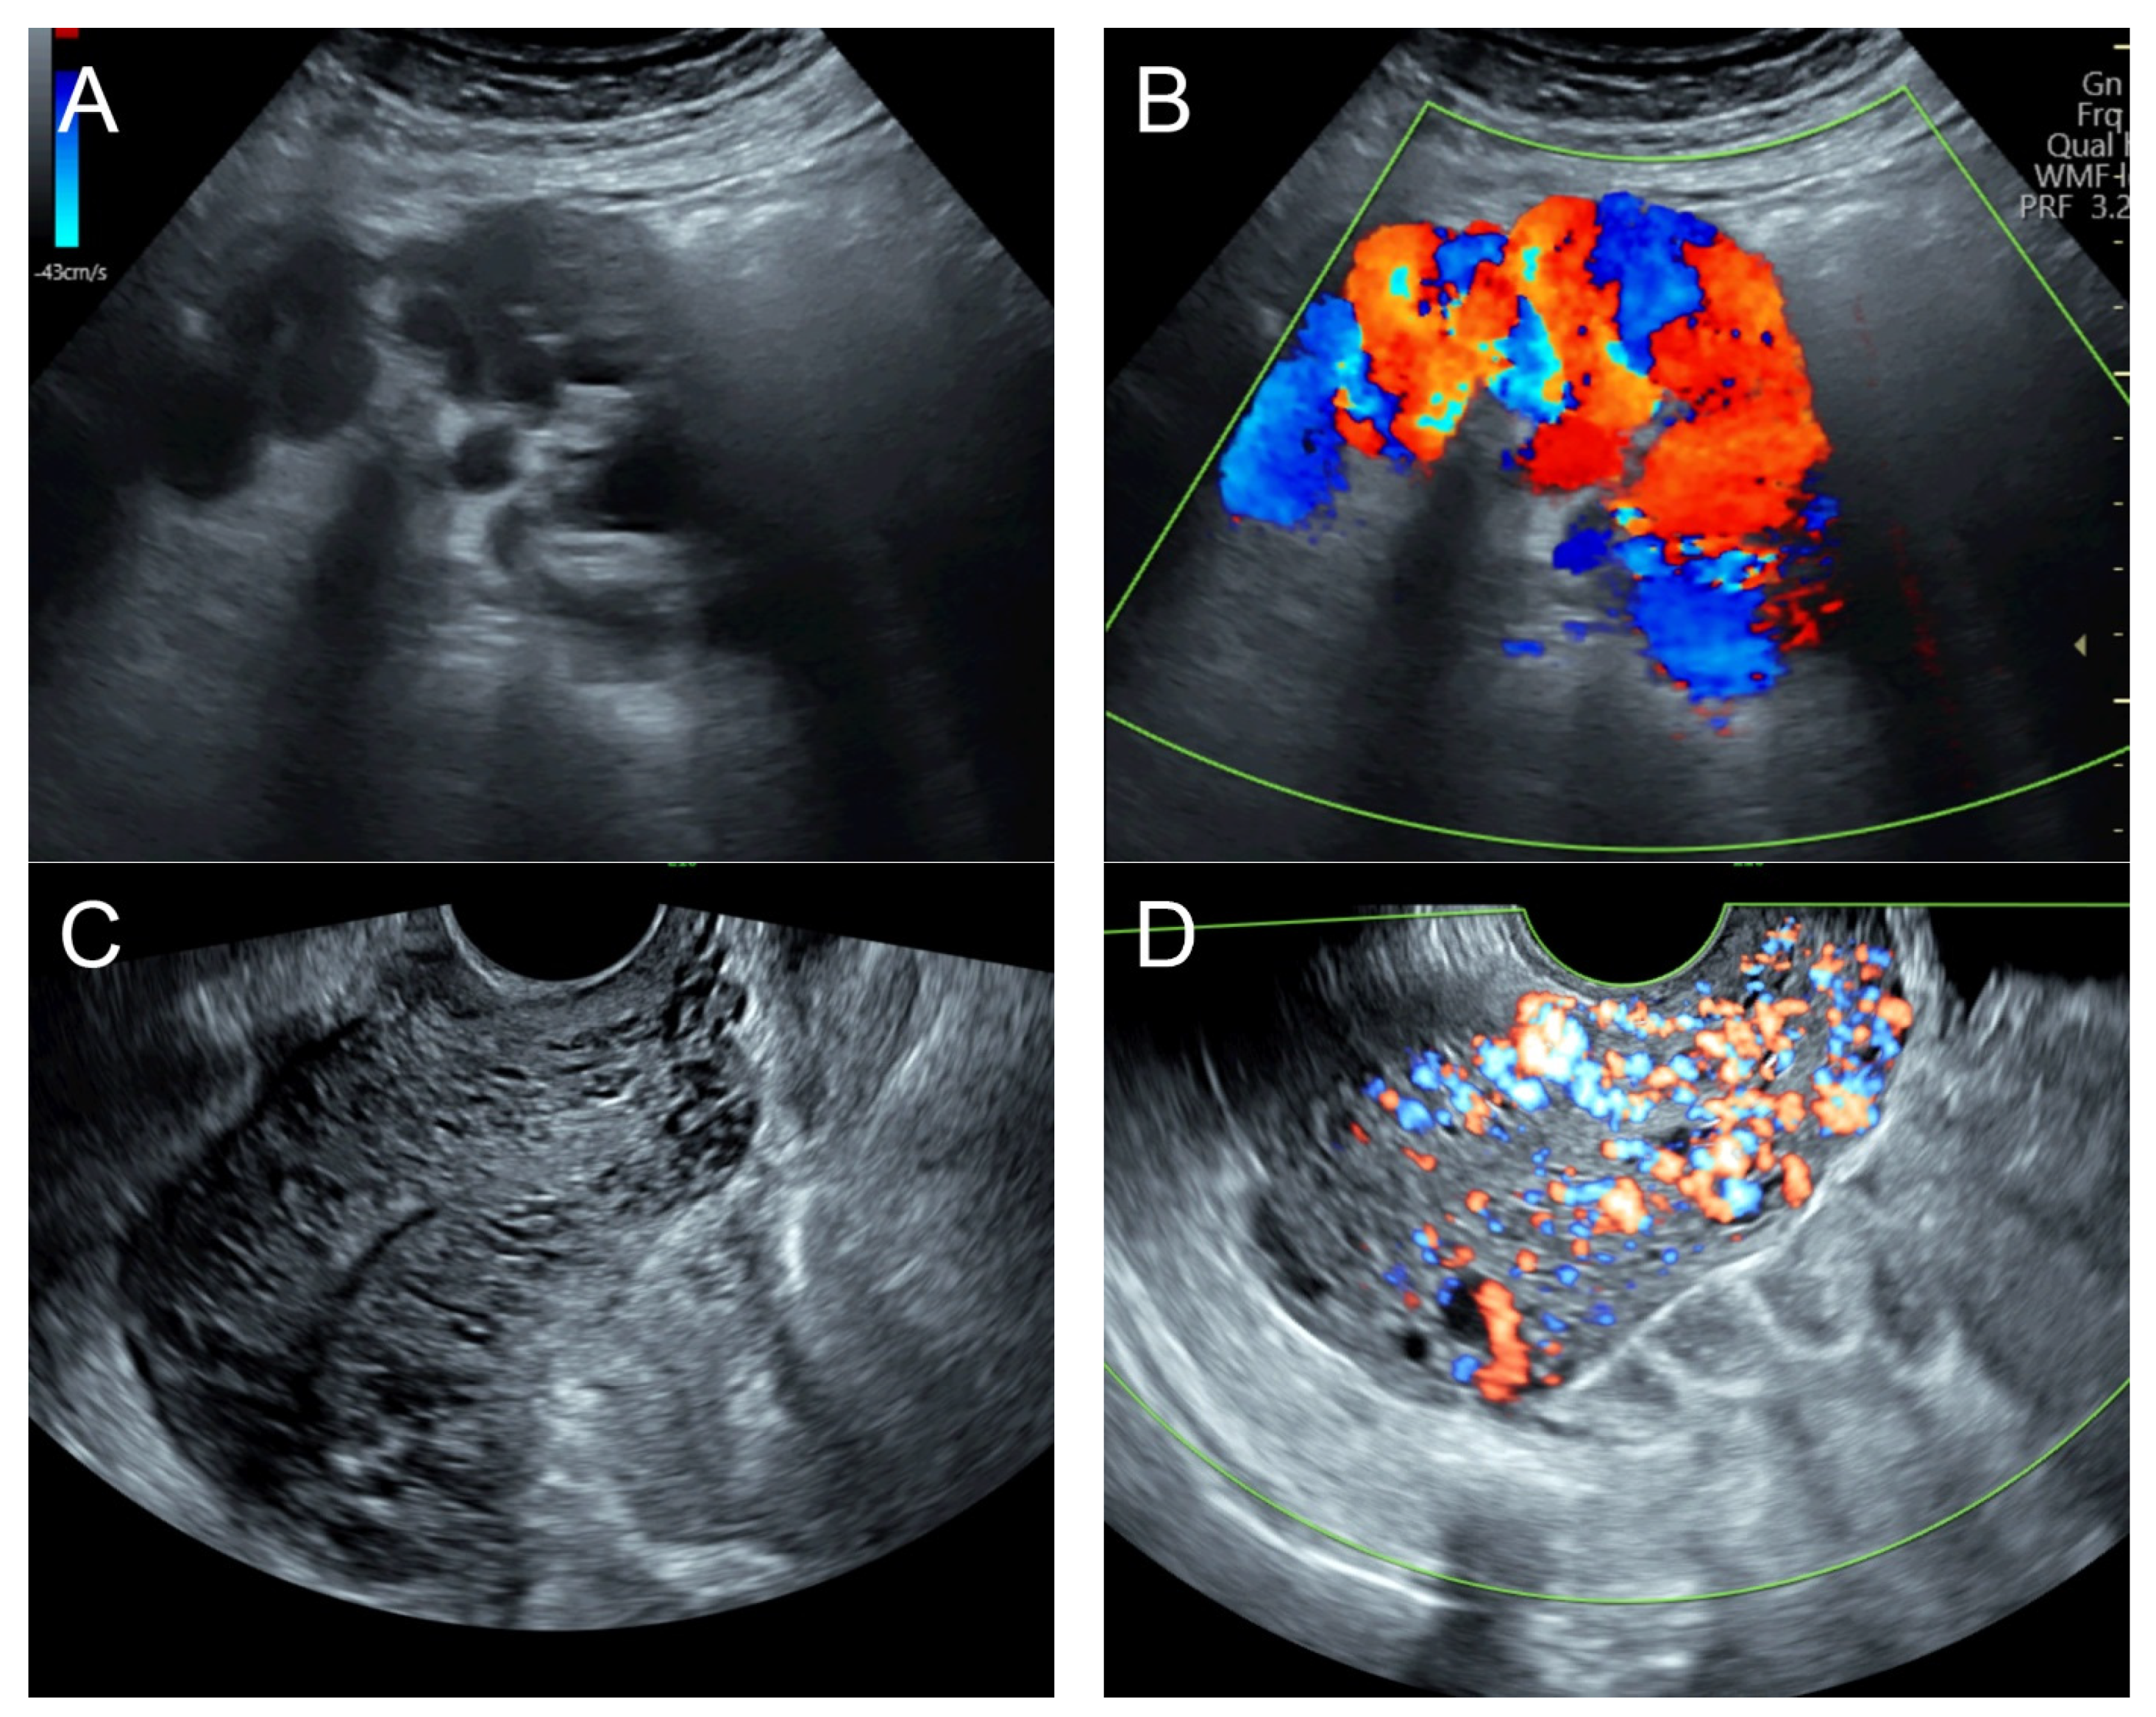

2. Case 1 (Figure 1)

Figure 1. (AC) Transabdominal grayscale ultrasound: cross-sectional, sagittal, and oblique scans of the uterus showed heterogeneous soft tissue content, like pieces of conceptive product in the uterine cavity; ill-defined endometrial–myometrial interface; hypoechoic lacunae varying in size in the non-specific tissue content, mainly localized at the left anterior wall. (D) Color flow mapping with a relatively high pulse repetition frequency of 3.2 kHz (applied to the same image (C)) showed hyper-vascularized lesions in the myometrium; multidirectional flow, mainly localized at the left anterior wall; and some cystic spaces of no flow, indicating lysed blood in the cavity. (E) Spectral Doppler ultrasound showed a high peak systolic velocity (approximately 60 cm/s). The sonographic diagnosis was uterine AVM. The main differential diagnoses were incomplete abortion (conceptive products) and gestational trophoblastic disease. (F) CTA during uterine embolization revealed hypervascularity and tortuous arterial anatomy enhancing a dilated vascular pouch overlying the endometrium of the uterus with feeding via the bilateral uterine arteries and draining via the internal iliac veins, confirming uterine AVM; low blood content in the uterine cavity without evidence of active contrast extravasation.

Management: Initial therapy included blood transfusion, tranexamic acid administration, and intrauterine tamponade with a Foley catheter balloon, resulting in less but continued bleeding. Emergency uterine artery embolization on both sides, using glue (Glubran 2 cyanoacrylate) mixed with Lipiodol (iodized oil), was successfully performed. The follow-up abdominal CTA at 8 weeks after the procedure showed no residual AVM, and the patient was healthy with no longer abnormal bleeding at 3-year follow-up.